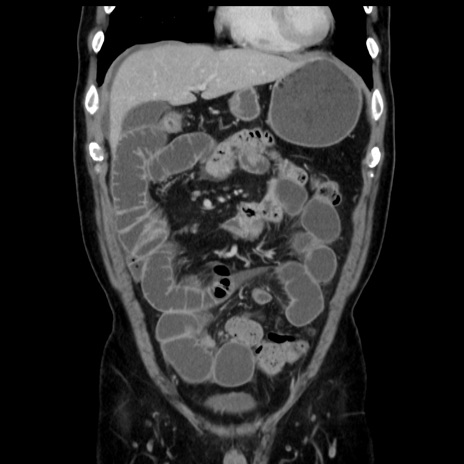

症例16(冠状断像)

【症例】 70歳代男性

【主訴】 腹痛、嘔吐

【現病歴】 約1ヶ月前より間欠的に腹痛と嘔吐あり、当院消化器内科を受診したところCTで多発する肝臓のLDAを指摘され、精査中であった。以降は消化器症状は安定していたが、2日前より嘔気と腹痛があり、同日より排便・排ガスが消失した。改善認めず、 本日、救急外来を受診した。

【既往歴】 大腸ポリープ切除後。

【身体所見】意識清明・会話良好、BT 36.3℃、BP 127/80mmHg、 P 80bpm、腹部:膨満あり、平坦・軟、上腹部正中および下腹部正中に圧痛あり、反跳痛なし、筋性防御なし。

【データ】WBC 7200、CRP 0.77